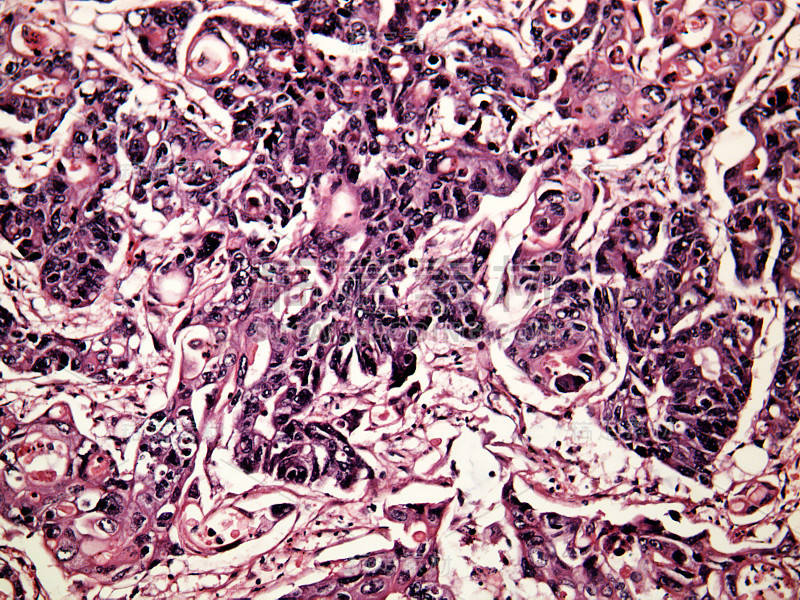

一个人的肝癌详情